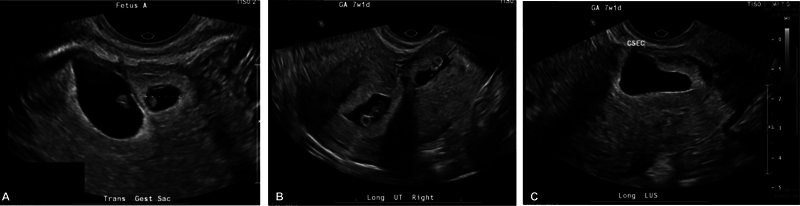

异位三胎妊娠、剖宫产瘢痕异位妊娠和子宫消融术后妊娠都是罕见的情况,会导致自然流产、宫内胎儿死亡、早产、胎盘异常和子宫破裂等重大疾病。一名 30 多岁的女性(G6P4014)曾做过子宫消融术,出现月经推迟和阴道点滴出血,造影显示两次宫内妊娠(其中一次有胎心活动),一次在剖宫产疤痕处活胎。医生对患者进行了广泛的咨询,让她了解自己和胎儿面临的风险,并讨论了各种治疗方案,包括预产期管理和终止妊娠。患者接受了不复杂的扩张刮宫术和双侧输卵管切除术,术后当天就出院回家,情况稳定。本病例强调了合并症的潜在复合效应,这些合并症会给咨询和管理带来困难。要点 接受子宫内膜消融术的患者应经过仔细挑选,并在高效避孕方面进行广泛咨询。许多情况都会对产妇的健康造成严重威胁,因此有必要讨论终止妊娠。

Heterotopic triplet pregnancy, cesarean scar ectopic pregnancy, and pregnancy following uterine ablation are all rare events that confer significant morbidity including spontaneous abortion, intrauterine fetal demise, preterm labor, abnormal placentation, and uterine rupture. A woman in her 30s, G6P4014, with a history of uterine ablation presented with delayed menses and vaginal spotting with imaging showing two intrauterine pregnancies (one with cardiac activity) and one live pregnancy at the cesarean scar. The patient was extensively counseled on risk to her and to the pregnancies; treatment options were discussed including expectant management and termination of pregnancy. The patient underwent an uncomplicated dilation and curettage with bilateral salpingectomy and was discharged home the day of the procedure in stable condition. This case highlights the potential compound effect of comorbid conditions that can pose difficulty in counseling and management. Key Points Patients undergoing endometrial ablation should be carefully selected and counseled extensively on highly effective contraception.Suspected cesarean scar pregnancies should be carefully evaluated early in gestation. Management should include thorough counseling and may be indivisualized.Many conditions pose a significant threat to maternal health and warrant a discussion of termination, which should be widely availaible and safe for all who need and/or desire it.